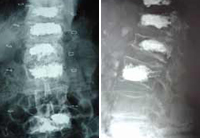

Kyphoplasty with balloon performed on five levelsby Dr. Morgenstern. Female patient with age 80 years, with inmediate erect walking after the intervention. |